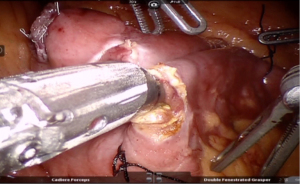

Marked bowel at 250 cm is hitched to anterior abdominal wall. Retro duodenal tunnel is meticulously dissected following which transaction is done at the level of D1 (Figure 27).

Duodeno-ileostomy is done using 3-0 barbed absorbable suture in a hand sewn fashion at 250 cm mark using 3-0 absorbable barbed suture (Figure 28).